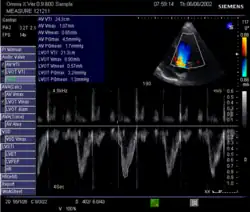

Echocardiography is a non-invasive method of quantifying cardiac output using ultrasound. Two-dimensional (2D) ultrasound and Doppler measurements are used together to calculate cardiac output. 2D measurement of the diameter (d) of the aortic annulus allows calculation of the flow cross-sectional area (CSA), which is then multiplied by the VTI of the Doppler flow profile across the aortic valve to determine the flow volume per beat (stroke volume, SV). The result is then multiplied by the heart rate (HR) to obtain cardiac output. Although used in clinical medicine, it has a wide test-retest variability.[9] It is said to require extensive training and skill, but the exact steps needed to achieve clinically adequate precision have never been disclosed. 2D measurement of the aortic valve diameter is one source of noise; others are beat-to-beat variation in stroke volume and subtle differences in probe position. An alternative that is not necessarily more reproducible is the measurement of the pulmonary valve to calculate right-sided CO. Although it is in wide general use, the technique is time-consuming and is limited by the reproducibility of its component elements. In the manner used in clinical practice, precision of SV and CO is of the order of ±20%.